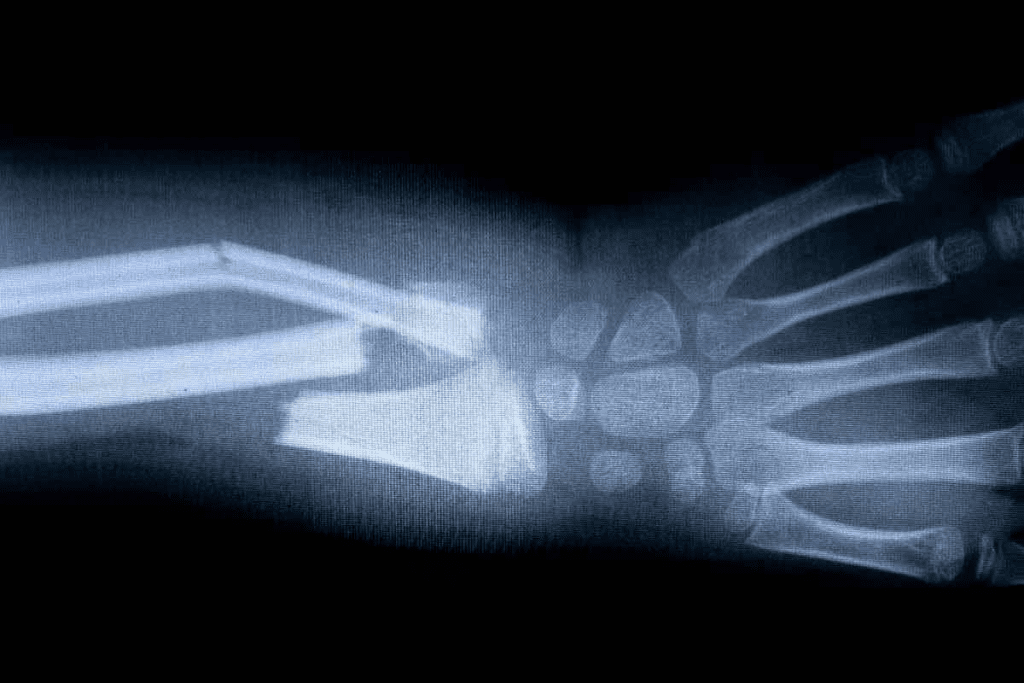

Cause #1: Fractures and Traumatic Bone Injuries

Bone scans are great for finding fractures and bone injuries. They show where the bone is not working right. This helps doctors plan the best treatment.

Acute vs. Healing Fractures on Bone Scan

Fractures show up on bone scans because of the bone’s repair work. New fractures have a lot of activity. Healing fractures show less activity as they mend.

It’s important to tell if a fracture is new or healing. Acute fractures need quick treatment and pain relief. Healing fractures need careful watching and maybe rehab to heal right.

Timeline of Uptake Following Bone Trauma

How fast a bone scan shows activity after an injury depends on the injury. Usually, activity goes up in 24-48 hours, peaks in 2-4 weeks, and then goes down as the bone fixes itself.

| Time Frame | Uptake Pattern | Clinical Significance |

| 0-48 hours | Increased uptake | Initial response to injury |

| 2-4 weeks | Peak uptake | Active bone repair |

| 4-6 months | Gradual decrease in uptake | Bone healing and remodeling |

Knowing this timeline helps doctors understand bone scans better. It helps match the scan results with what the patient is feeling and going through.